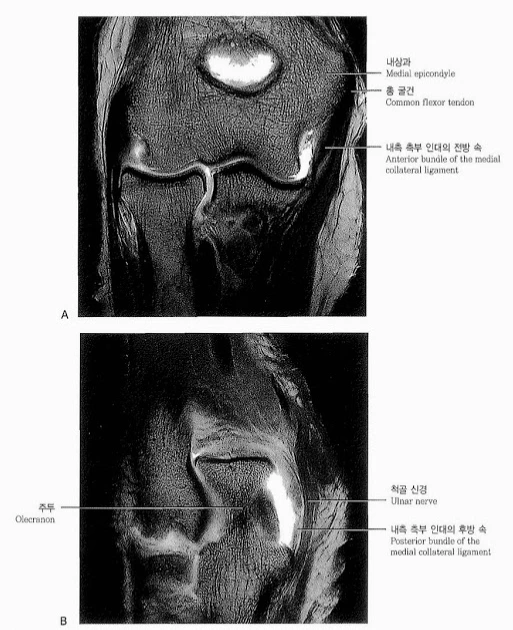

내측 측부 인대는 이렇게 생겼습니다. 전방속 후방속 횡속으로 불리우는 3가지 인대로 되어 있으며, 앞 뒤 그리고 측면으로 관절을 튼튼하게 유지시켜 줍니다. 이런 인대가 일부라도 파열되게 되면, 인대가 느슨해져서 덜렁거리게 되는데 이를 관절의 불안정성이라고 합니다. 관절의 불안정성이 생기면 퇴행성 관절염으로 인해서 팔꿈치 관절이 붓고 아프고 커질 수 있으니 초기에 치료로 잡아야합니다.

실제 정상적인 팔꿈치 관절을 MRI로 찍으면 저렇게 검게 나오게 됩니다. 인대에는 질긴 성분으로 물이 많지 않기 때문에 검게 나옵니다. MRI가 하얗게 나온다는 것은 물이 많다는 것인데요, 물이 많은 것은 주로 염증 때문입니다. 즉 염증이 없으면 하얗게 나올 일이 없습니다. 다만, 무조건 하얗게 나오는 것이 모두 염증은 아니고 지방이나 수핵 수분 등 다양한 원인이 있으니 의료진의 의견을 잘 들어야합니다.